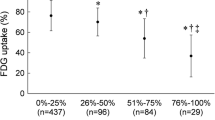

Patients were followed for 47 months (range 5-54 months). MACE occurred in nine patients (unstable angina in 6, recurrence of acute MI in 1, cardiac death in 1, late PCI in 1). In the univariate Cox regression analysis, increased SUVmax of RCA PCAT [HR 6.273, 95% CI (1.297, 30.343), P = .022] and age > 60 [HR 6.268, 95% CI (1.296, 30.314), P = .022] showed a correlation with a higher risk of MACE. In multivariable Cox regression analysis, they remained significant [increased SUVmax of RCA PCAT: HR 5.198, 95% CI (1.058, 25.537), P = .042; age > 60: HR 5.195, 95% CI (1.057, 25.531), P = .043]. The results of univariate and multivariate Cox regression analysis are shown in Table 2 and Figure 4.